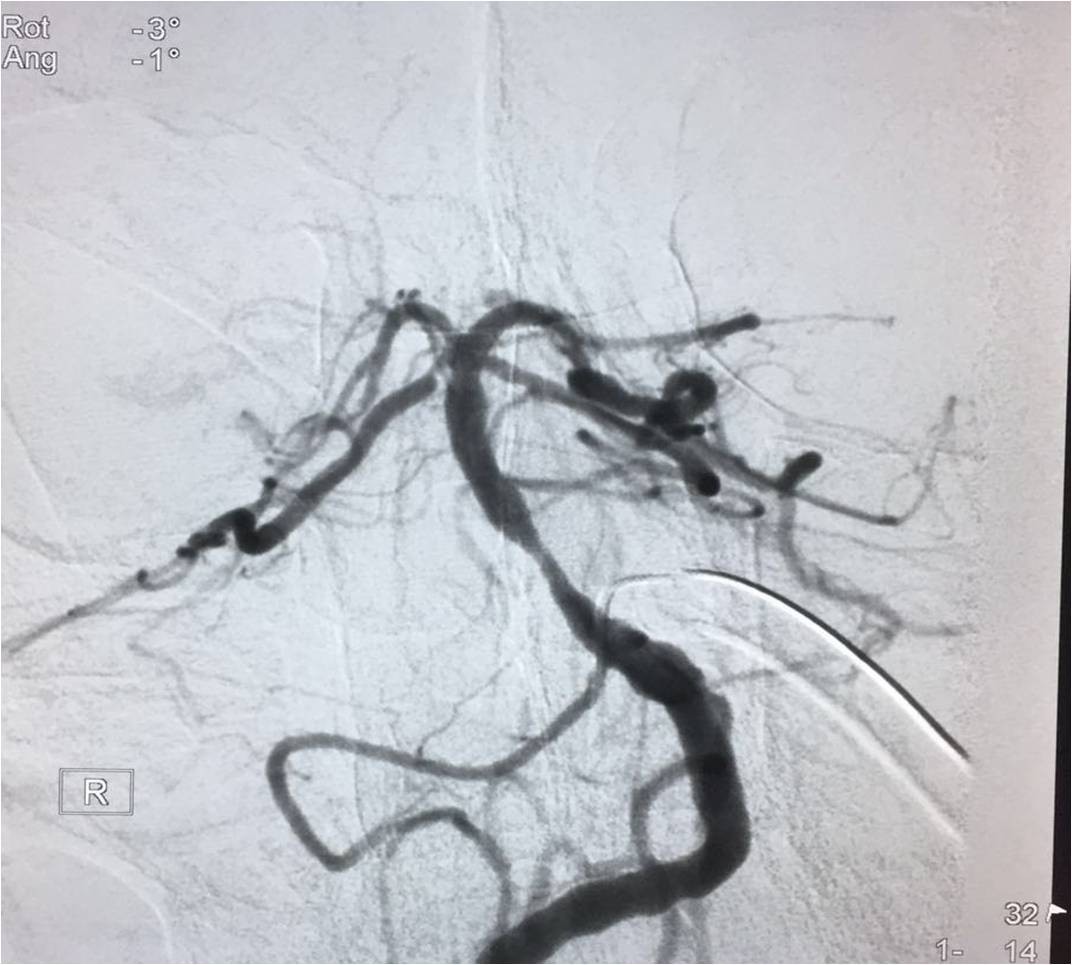

▼复查造影。

治疗效果、预后及随访情况:患者入院后严格按照《2015急性缺血性卒中血管内治疗中国指南》给予诊断治疗。患者术前NIHSS评分≥30分,术后第一天NIHSS评分19分,病情未进一步加重,肢体肌力恢复到3级,神志较前好转,病情稳定,进一步康复后,可恢复生活自理。